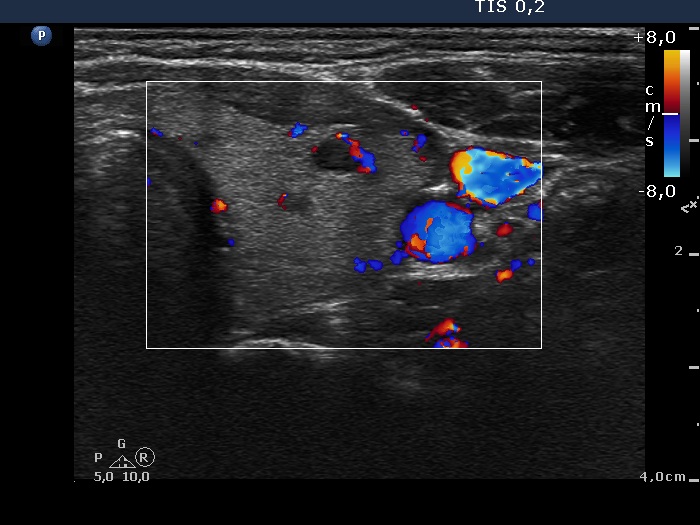

Consecutively operated patients with autoimmune thyroid disease - case 58 (1764) (ultrasonographic picture 6)

The patient is euthyroid without thyrostatic therapy

Left lobe, longitudinal scan, color Doppler mode. The vascularization is decreased.